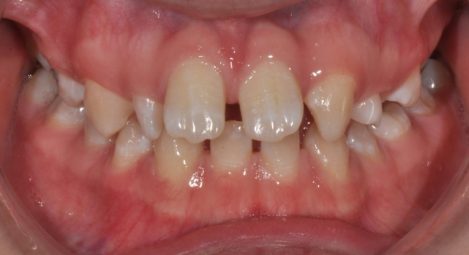

Ортодонтско лечение при множествена хиподонтия. Клиничен случай.

Статията обсъжда клиничните аспекти на проблема – множествена хиподонтия. Решението и планът на лечение при тези пациенти включват дългосрочни цели и съобразяване с костното развитие на пациента както до завършване на растежа му, така и при неговото остаряване. Често лечението на тези клинични случай завършват с протетичното им възстановяване. Затова ортодонтското лечение трябва да е съобразено с крайното дефинитивно възстановяване на съзабието.